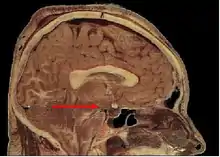

Гипоталамус является частью промежуточного мозга. Он образует основание и стенки нижней части третьего желудочка. Название своё он получил от греч. гипо- (под, внизу) и таламос (чертог, спальня), так как он располагается под таламусом. Гипоталамус отделён от таламуса гипоталамической бороздой (лат. sulcus hypothalamicus). Анатомические границы гипоталамуса определены недостаточно чётко, что связано с тем, что некоторые группы клеток заходят в соседние области, а также с некоторой неопределённостью в терминологии[4]. Считается, что спереди (рострально) гипоталамус ограничен терминальной пластинкой (лат. lamina terminalis), а его задняя (каудальная) граница — воображаемая линия от задней комиссуры (лат. commissura posterior) до каудальной поверхности сосцевидных тел. Дорсолатерально гипоталамус доходит до медиального края мозолистого тела[5].

В нижней части гипоталамуса выделяются такие структуры, как сосцевидные тела (лат. corpus mamillare), серый бугор (лат. tuber cinereum) и воронка (лат. infundibulum). Воронка отходит от серого бугра, средняя часть воронки приподнята и называется срединным возвышением (лат. eminentia mediana), которое в некоторых классификациях относят к серому бугру, а в некоторых — к нейрогипофизу[6]. Срединное возвышение содержит кровеносные сосуды, переносящие выделяемые гипоталамусом вещества в гипофиз. Нижняя часть воронки переходит в ножку гипофиза.